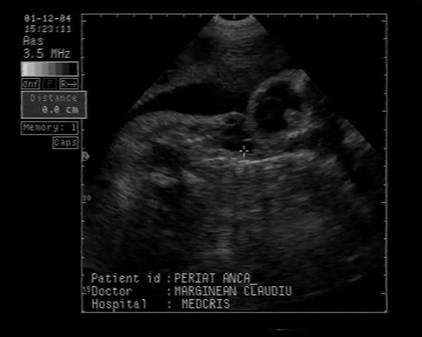

Fig. nr.252 Limfangiofibrom orofaringian la 16 sapt,.formatiune in fata oaselor masivului facial.

Fig. nr.253 Limfangiofibrom orofaringian diagnosticat prin ecografia transvaginala ( acelasi caz ca in figura precedenta ). Inaintea fetei se evidentiaza o formatiune aparent chistica.